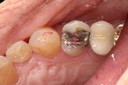

Ted Kanamori #29, 30, 31 pre-op

Ted Kanamori #29, 31 caries removal

Ted Kanamori #31 prep

Ted Kanamori #29 prep

Ted Kanamori #29, 31 casting try in

Ted Kanamori #30 amalgam removal

Ted Kanamori #30 prep

Ted Kanamori #29, 31 finish, #30 prep

Ted Kanamori #30 finish